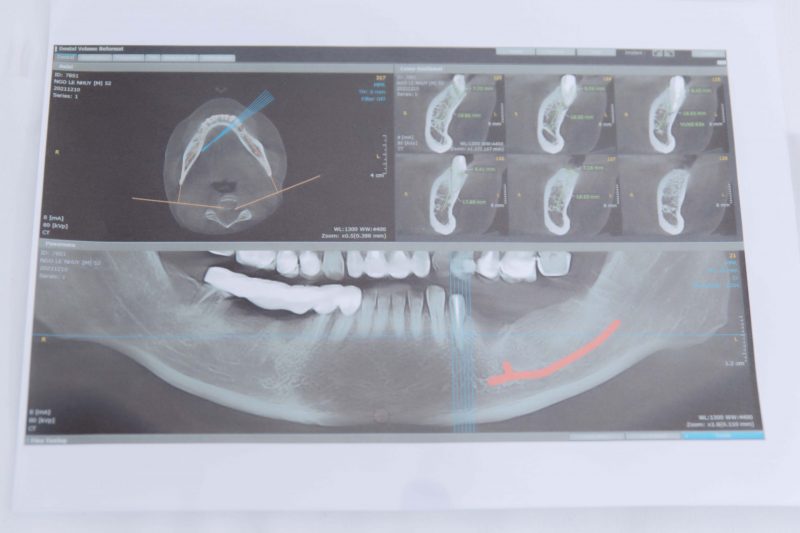

Bệnh nhân được chẩn đoán qua phim CT trước phẫu thuật đặt implant